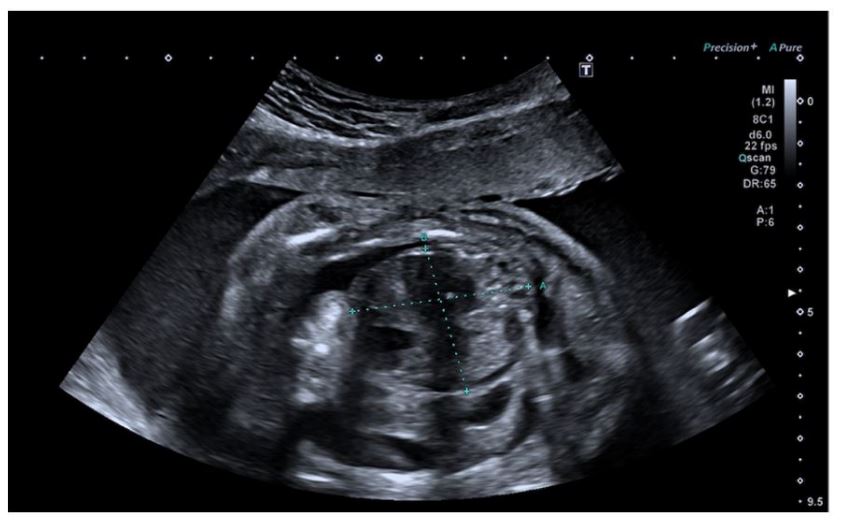

At the 31-week US, the lesion had increased in size to 59 x 40 x 36 mm and showed cystic, solid, and calcified components. Mild pleural effusion persisted, and additional findings included subcutaneous edema and polyhydramnios (Figure 3). Cervical examination revealed a shortened cervix measuring 19 mm.

Figure 3 Ultrasound at 31 weeks showing a heterogeneous thoracic lesion with associated pleural effusion.